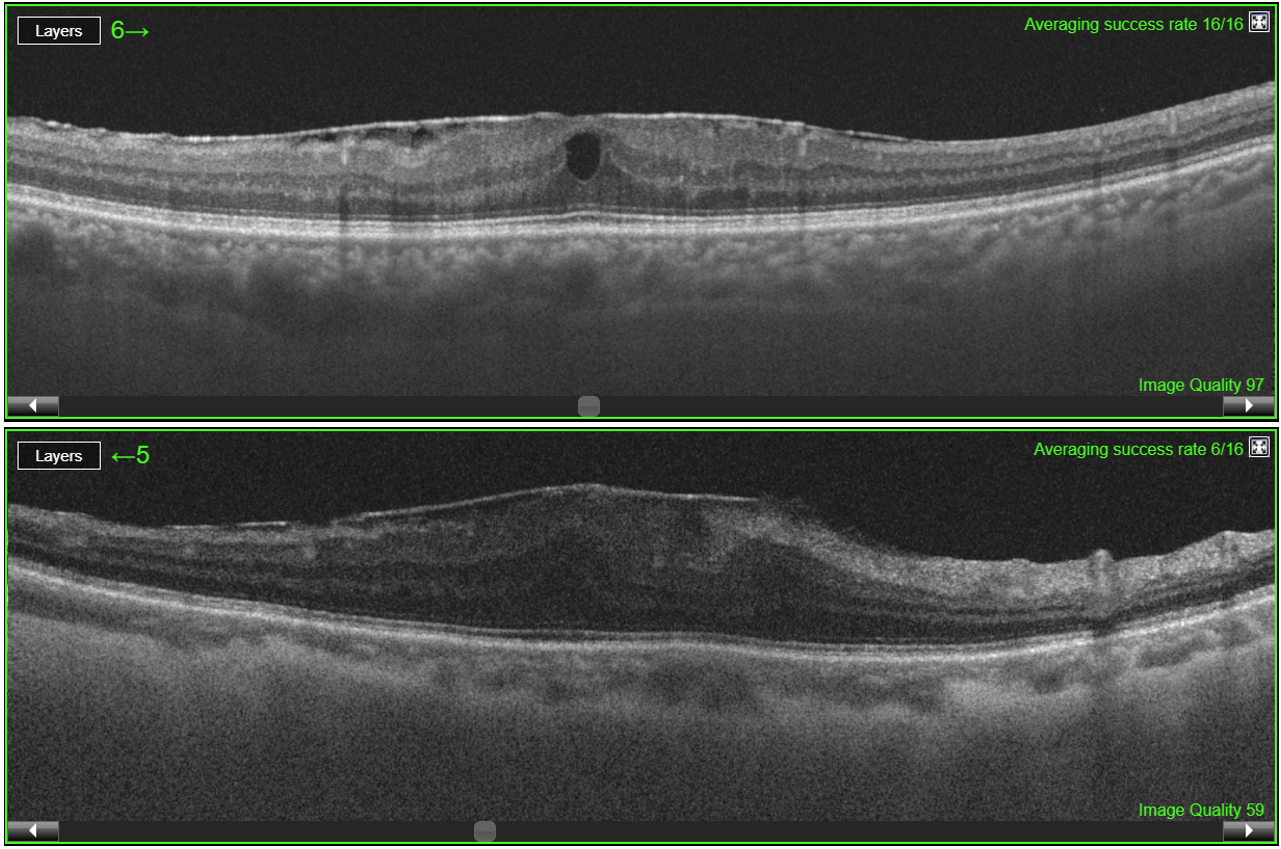

Among 700 patients, 438 patients who underwent cataract surgery had cystoid macular oedema (NCMO=274) or retinal detachment (NRD=164), and NH=262 patients did not have any retinal diseases/complications. The dataset consisted of 700 OCT B-scan macular images obtained post-surgery (figure 1), 80 % of them were randomly selected for the training of SVM, whereas 20 % of the data were used to test the algorithm (table 1).

Figure 1. OCT B-scans of cystoid macular oedema (top) and retinal detachment (bottom) after cataract surgery